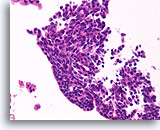

Invasief slecht gedifferentieerd carcinoom, Borst FNA, Celblok.

Dit infiltrerende hooggradige carcinoom heeft een hoge mate van bijmenging van lymfocyten.

20X

Invasief slecht gedifferentieerd carcinoom, Borst FNA, Celblok.

Dit infiltrerende hooggradige carcinoom heeft een hoge mate van bijmenging van lymfocyten.

20X